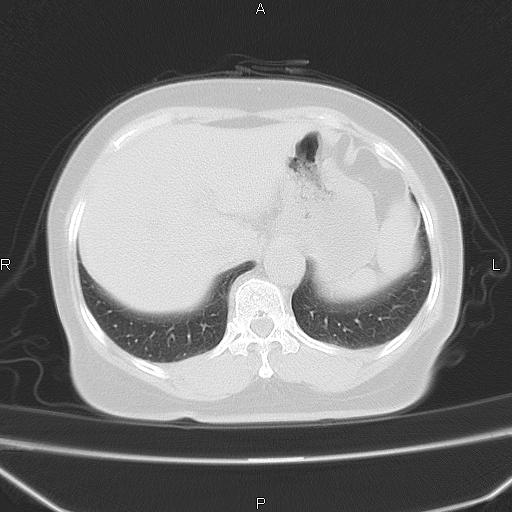

胸腺瘤

女、63Y 双眼睑下垂,早轻晚重。 胸腺瘤???

结果胸腺瘤